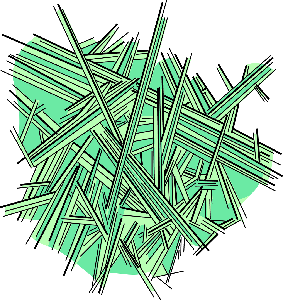

Detailreiche Fotografien aus der medizinischen Praxis ergänzen die Texte; moderne, genaue,

wissenschaftliche Zeichnungen geben Einblick in die Anatomie und die Funktion der Lunge und

anderer Organe.